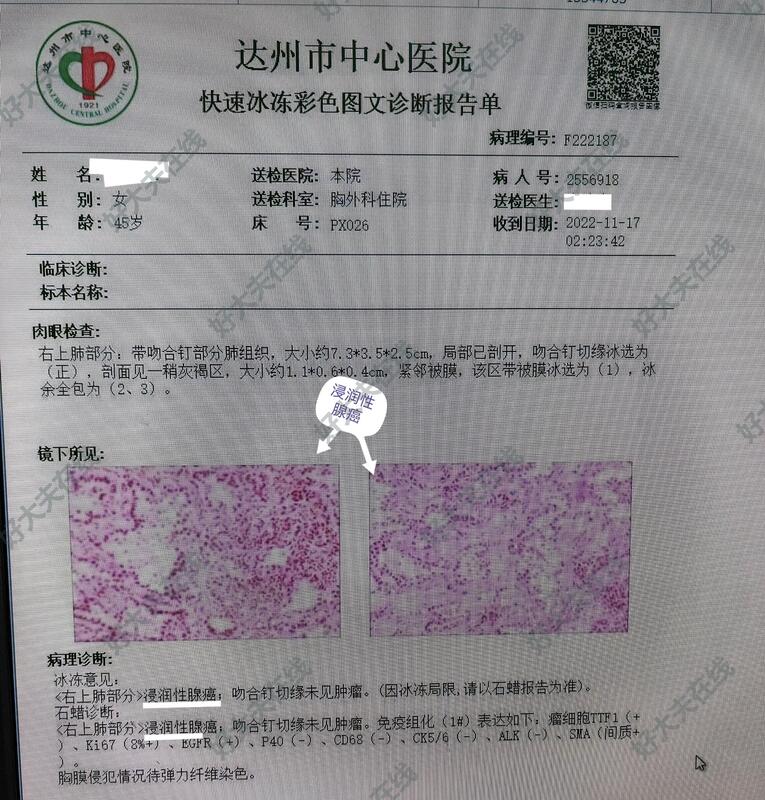

图1-5,女性,45岁,体检发现右肺上叶前段结节,亚实性(磨玻璃)结节、毛刺、分叶、胸膜牵拉等,短期随访结节不消散。胸腔镜微创手术切除,病理报告为肺浸润性腺癌。

例1,45岁,女性患者,病理报告系浸润性肺腺癌,建议完善基因检测,查找靶点,便于指导随访观察,目前,暂不考虑化疗等。